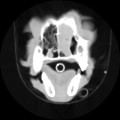

CT - lebka